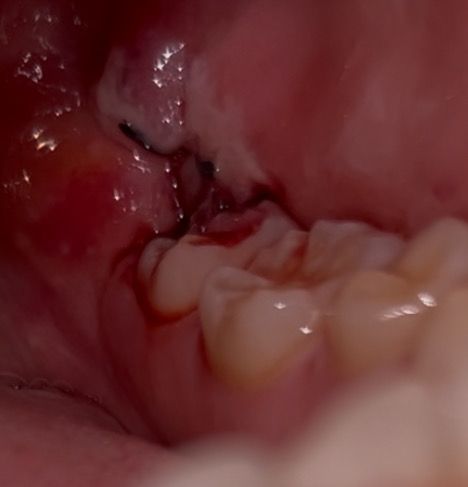

매복사랑니 발치 3일차 출혈 괜찮은건가요?

발치 3일차고 통증은 아직 있습니다 ㅠㅠ

피가 멈췄다가 코감기가 걸려서 재채기를 10분에 한 번씩 하더니 다시 피가 나기 시작합니다

• 2번 째 사진

피가 약간 나는 정도는 문제가 되지 않으며 사진상에서도 특별히 문제가 보이지는 않습니다.

3일차 이정도면 정상적으로 아물고 있는 것입니다. 자극에 의해 피가 조금 스며 나와도 문제되지 않습니다.

아직은 지혈이 완벽히 되는건 아닌거 같습니다. 피가 조금씩 나오는건 괜찮지만, 계속해서 흐르면 치과에 가셔서 후처치를 받아보시는게 좋을것같습니다.

발치 후 약간의 출혈은 1주일 까지도 있을 수 있습니다. 큰 문제는 없어보이고요. 사진상으로도 특별히 이상은 없어보입니다.